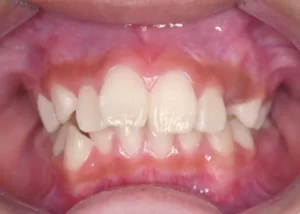

正面

- Before